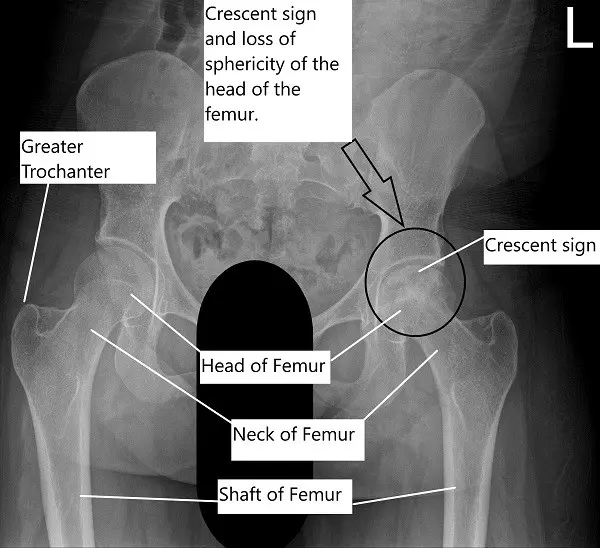

On radiological investigations, the X-ray of the left hip revealed avascular necrosis of the head of the femur with subchondral collapse visible in the form of a crescent sign. The X-ray of the right hip revealed a normal radiograph.

X-ray of the pelvis with both hip joints showing AVN of the left head of the femur.